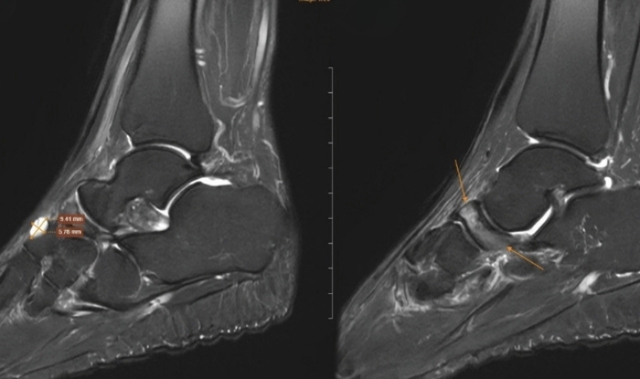

Tại cơ sở y tế, bác sĩ chỉ định chụp cộng hưởng từ để đánh giá tổn thương sâu. Kết quả, xương ghe bàn chân phải bị xẹp và biến dạng điển hình, kèm đặc xương dưới sụn và phù tủy rõ rệt. Ngoài ra, hình ảnh còn ghi nhận tổn thương thoái hóa khớp cổ chân trái, phù tủy xương sên, viêm dây chằng và dịch khớp cổ chân.

Nữ giáo viên đi khám đau cổ chân, bất ngờ phát hiện bị bệnh 'triệu người có một'- Ảnh 1.

Hình ảnh chụp MRI cho thấy những dấu hiệu đặc trưng của Hội chứng Mueller-Weiss ở chân phải.